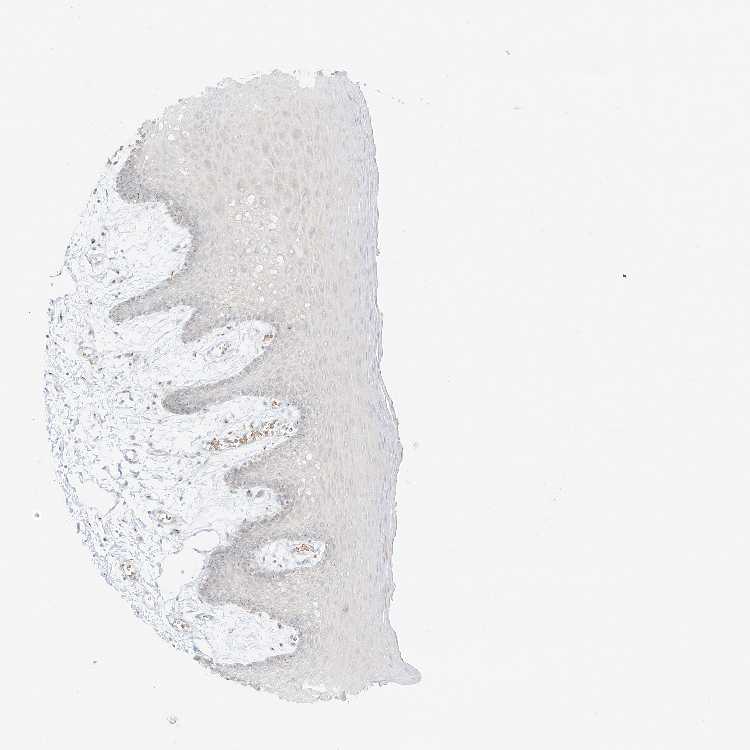

TISSUE PRIMARY DATA ORAL MUCOSA Show tissue menu

ORAL MUCOSA - Antibody stainingi

Antibody staining in the annotated cell types in the current human tissue is reported as not detected, low, medium, or high, based on conventional immunohistochemistry profiling in selected tissues. This score is based on the combination of the staining intensity and fraction of stained cells.

Each image is clickable and will lead to virtual microscopy that enables deeper exploration of all samples and also displays staining intensity scores, fraction scores and subcellular localization as well as patient and tissue information for each sample.

Antibody HPA035183

Squamous epithelial cells Medium